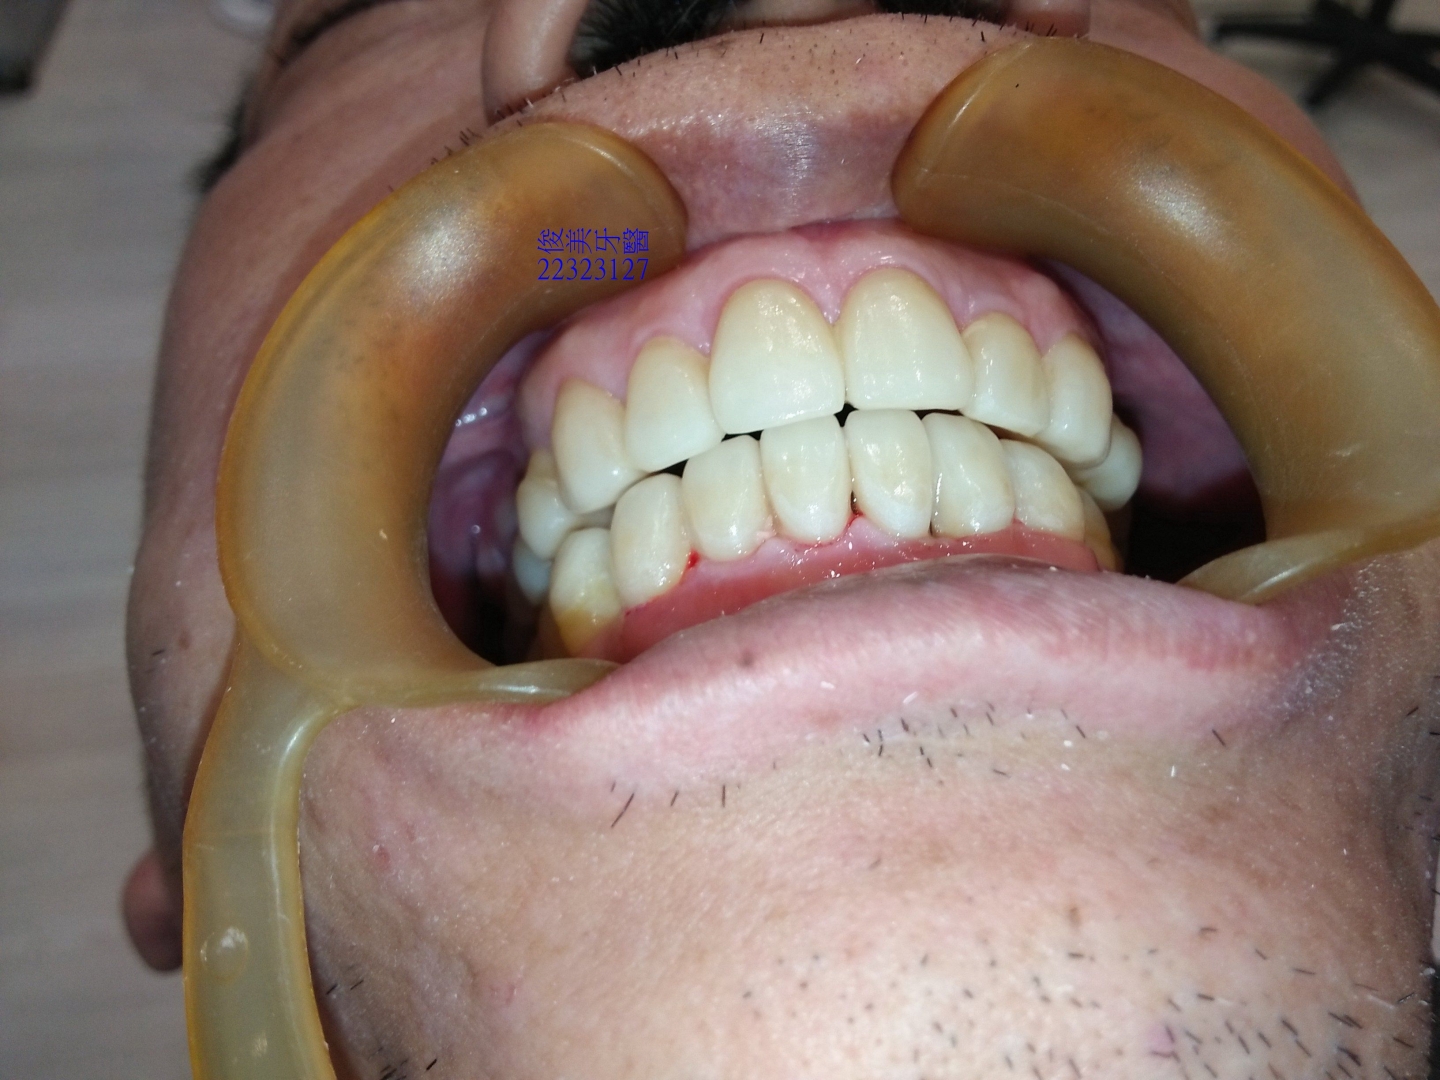

咬合狀況。